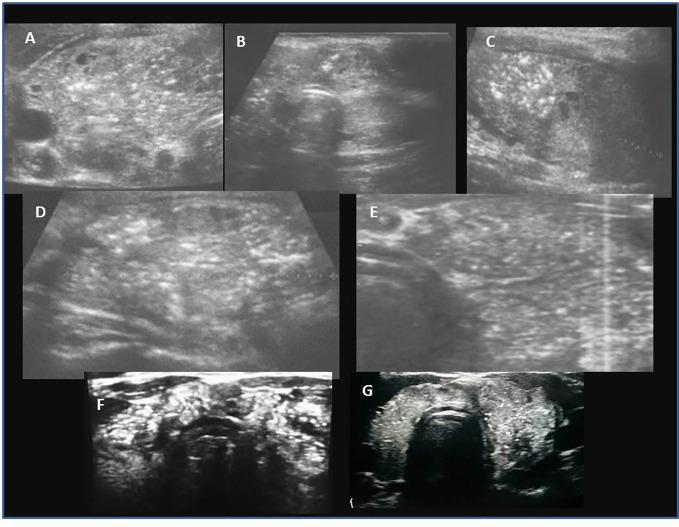

Ultrasound, laboratory and histopathological insights in diagnosing papillary thyroid carcinoma in a paediatric population: a single centre follow-up study between 2000-2022.

A retrospective analysis of medical records of 90 patients (69; 76.7% females). The mean age at PTC diagnosis was 13.8 years [range 6-18]. All patients were evaluated ultrasonographically before thyroid surgery. Thyroid nodules were categorised using the European Thyroid Imaging Reporting and Data System (EU-TIRADS PL), and cytopathology was assessed using Bethesda criteria. Neck ultrasound results and thyroid and autoimmune status were correlated with histopathological PTC assessment.

The coexistence of PTC and AIT was found in 48.9% (44/90) of patients. The percentage of AIT was increasing with age; AIT was present only in 1/3 of prepubertal, close to 50% in pubertal, and over 60% in adolescent patients. The youngest patients (aged <10 years old) presented more often with goitre and lymphadenopathy and less often with AIT than adolescents (15-18 years of age). There were no differences in TPOAb, TgAb, and TSH levels between the age subgroups. Presurgical TgAb levels were higher than those of TPOAb in the youngest patients. Histopathological analysis revealed that the solid subtype was observed more often in prepubertal children and diffuse sclerosing in children below 14 years of age, whereas the classic subtype dominated in late pubertal. Univariate and multivariate analyses revealed that lymph nodes metastases (LNM) were associated with PTC diameter and fT4 level, whereas extrathyroidal extension with age and angioinvasion with PTC diameter and age. The correlations between age and fibrosis, and the presence of psammoma bodies in malignant tissues were close to significant. We did not observe an association between TSH levels and the presence of autoimmunity and PTC variables.

In paediatric patients the natural course of PTC may be less aggressive in adolescent patients than in younger children (especially < 10 years of age). We suggest that pre-operative evaluation of paediatric patients with thyroid nodules could include apart from assessment of thyroid hormones, evaluation of TPOAb, TgAb, and TRAb together with comprehensive neck ultrasonography.